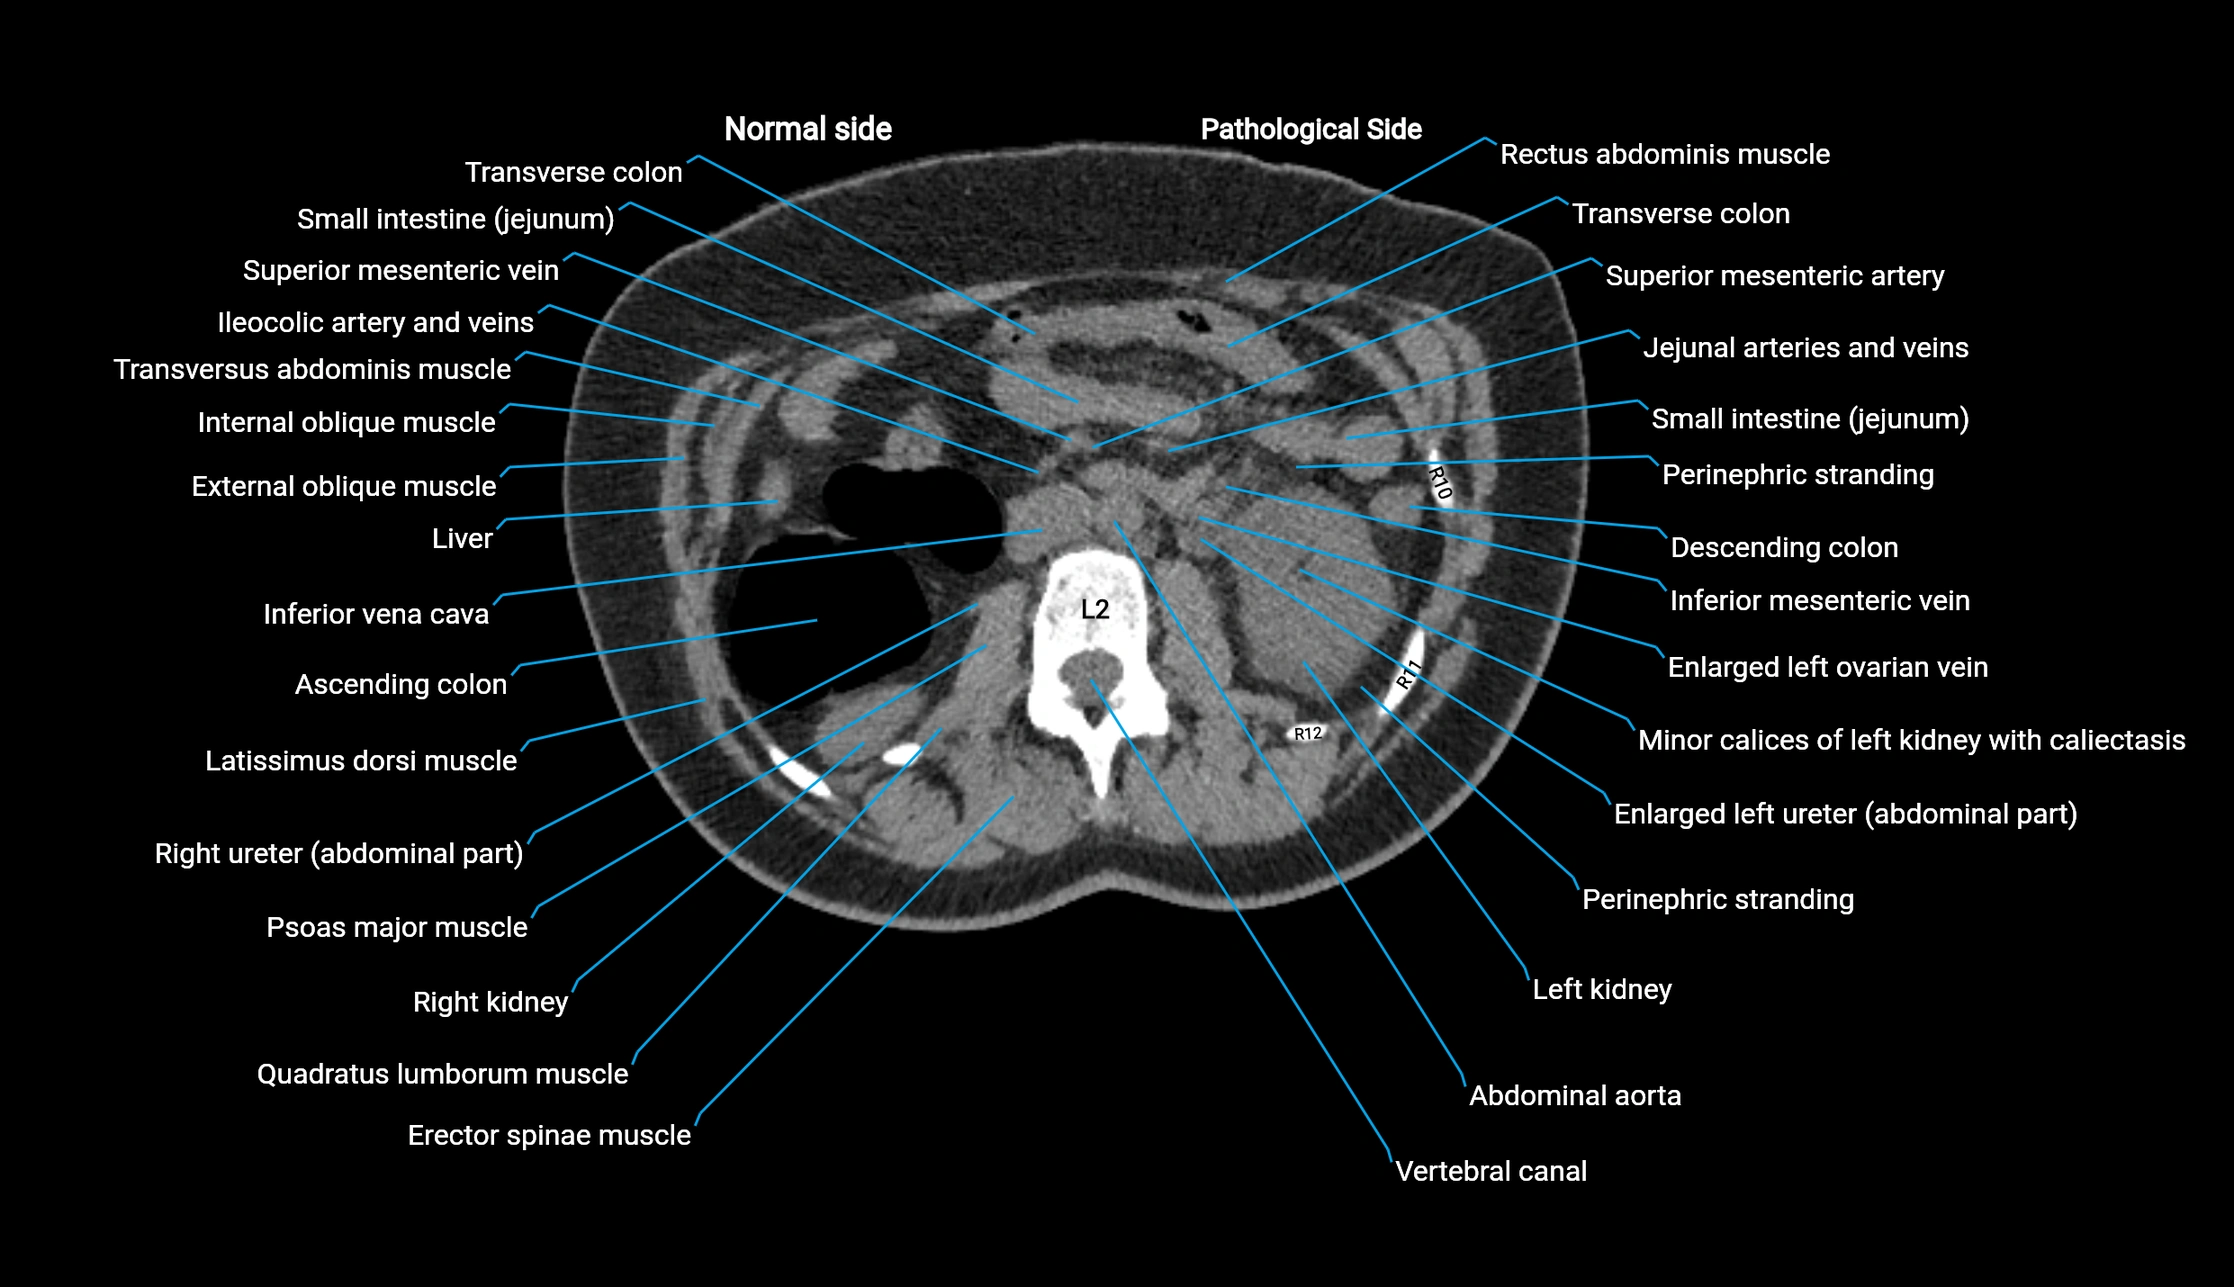

CT image

image